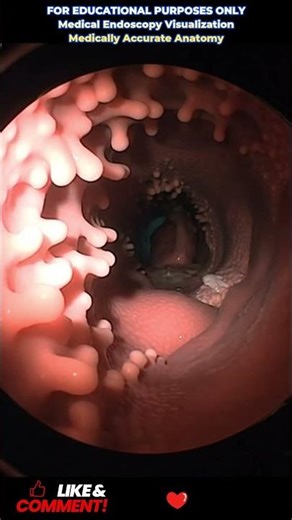

Endoscopy Procedure Explained | 3D Medical Visualization

This educational 3D medical animation explains how an endoscopy procedure is performed in a clear and simple way. The video shows the path of the endoscope through the digestive system using clean, non-graphic visuals. Designed for medical awareness and general education. Suitable for all audiences. #Endoscopy #MedicalEducation ...